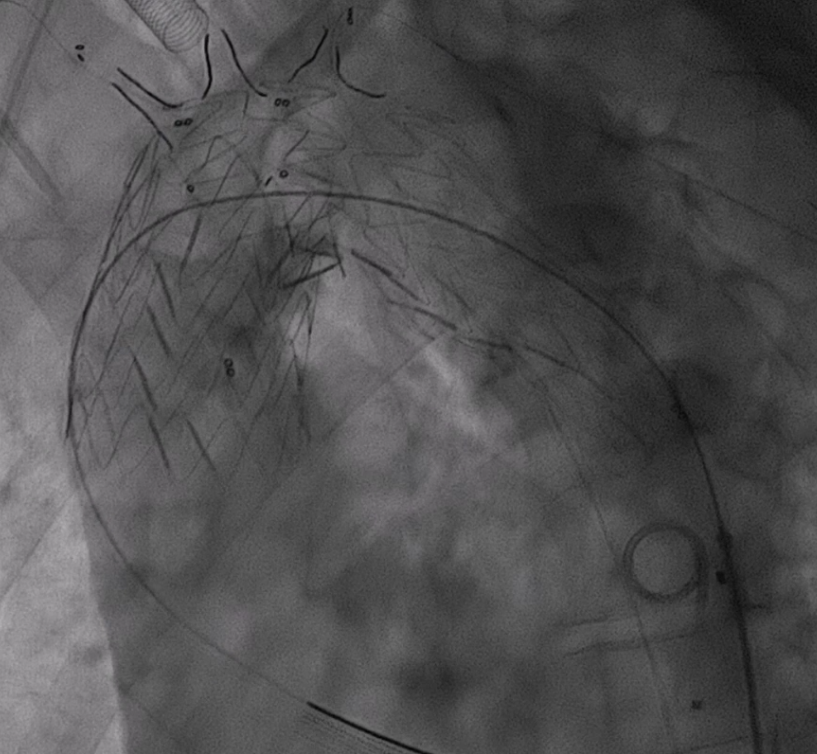

4. 支架输送与定位

根据详细测量数据,选用型号为 F46-40-45-191-16-14-14 FixTa一体化三分支主动脉覆膜支架支架系统。

将主导丝与导管准确卡入对应分线器卡槽内,撤出防缠绕导管内的导引导丝,各分支导管分别接入对应的分支导丝。主导丝连接支架输送系统,各牵引导丝从弓上引出并连接牵引器,通过牵引器保持适当张力,确保支架手柄编号与防缠绕导管手柄编号一致。

沿超硬导丝将主体缓慢送入主动脉弓部,透视下确保导丝无缠绕。

调整支架位置,确保主体分支支架对应无名动脉、左颈总动脉及左锁骨下动脉开口位置满意。

5. 支架释放与球囊预扩

释放支架主体,之后,头端后释放打开后将支架输送系统缓慢撤出。

分别经分支导丝送入球囊扩张支架分支覆膜部分,确保贴附良好。

6. 裸支架置入,球囊后扩张

于无名动脉、左颈总动脉及左锁骨下动脉开口位置处释放裸支架,维持血流通畅。

球囊后扩,优化支架形态及贴壁性,减少内漏风险。